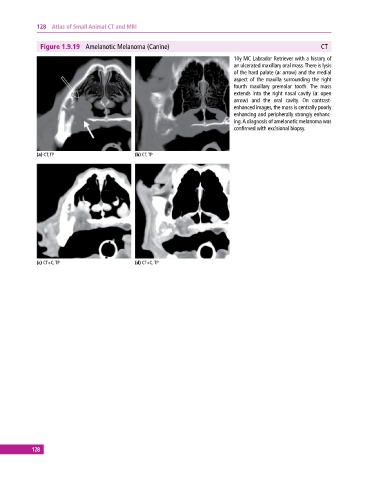

Figure 1.9.19 Amelanotic Melanoma (Canine) CT

10y MC Labrador Retriever with a history of

an ulcerated maxillary oral mass. There is lysis

of the hard palate (a: arrow) and the medial

aspect of the maxilla surrounding the right

fourth maxillary premolar tooth. The mass

extends into the right nasal cavity (a: open

arrow) and the oral cavity. On contrast‐

enhanced images, the mass is centrally poorly

enhancing and peripherally strongly enhanc

ing. A diagnosis of amelanotic melanoma was

confirmed with excisional biopsy.

(a) CT, TP (b) CT, TP

(c) CT+C, TP (d) CT+C, TP